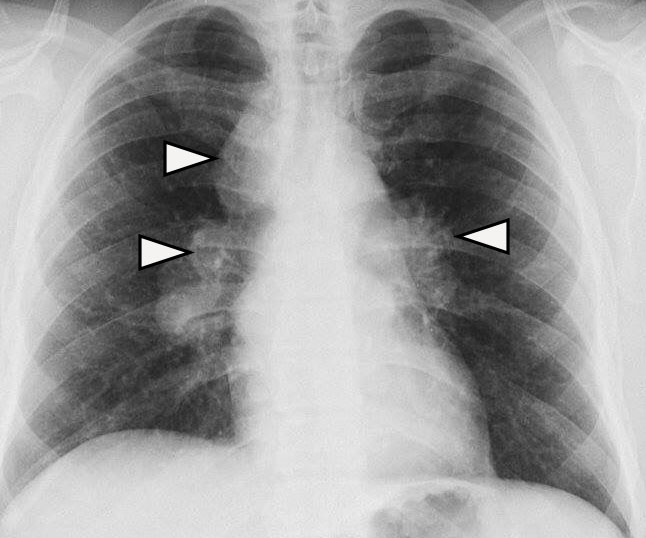

Sign of 1-2-3 (Garland's Triad)

It refers to a lymph node enlargement pattern characterized by right paratracheal and right and left hilar enlargement, suggesting sarcoidosis. Leo Henry Garland (1903-1966) was an Irish-born American radiologist who published his experience on radiographs of 36 cases of sarcoidosis in an article published in 1947. A combination of bilateral hilar and right paratracheal adenopathy was found in 13 cases, 7 with pulmonary alterations and 6 without, although at the onset of the disease it was present in approximately two thirds of the cases. Figure 2.1,7-11

Figure 2 Frontal chest x-ray shows lymph node enlargement pattern (white arrowhead) characterized by right paratracheal and right and left hilar enlargement, suggesting sarcoidosis.